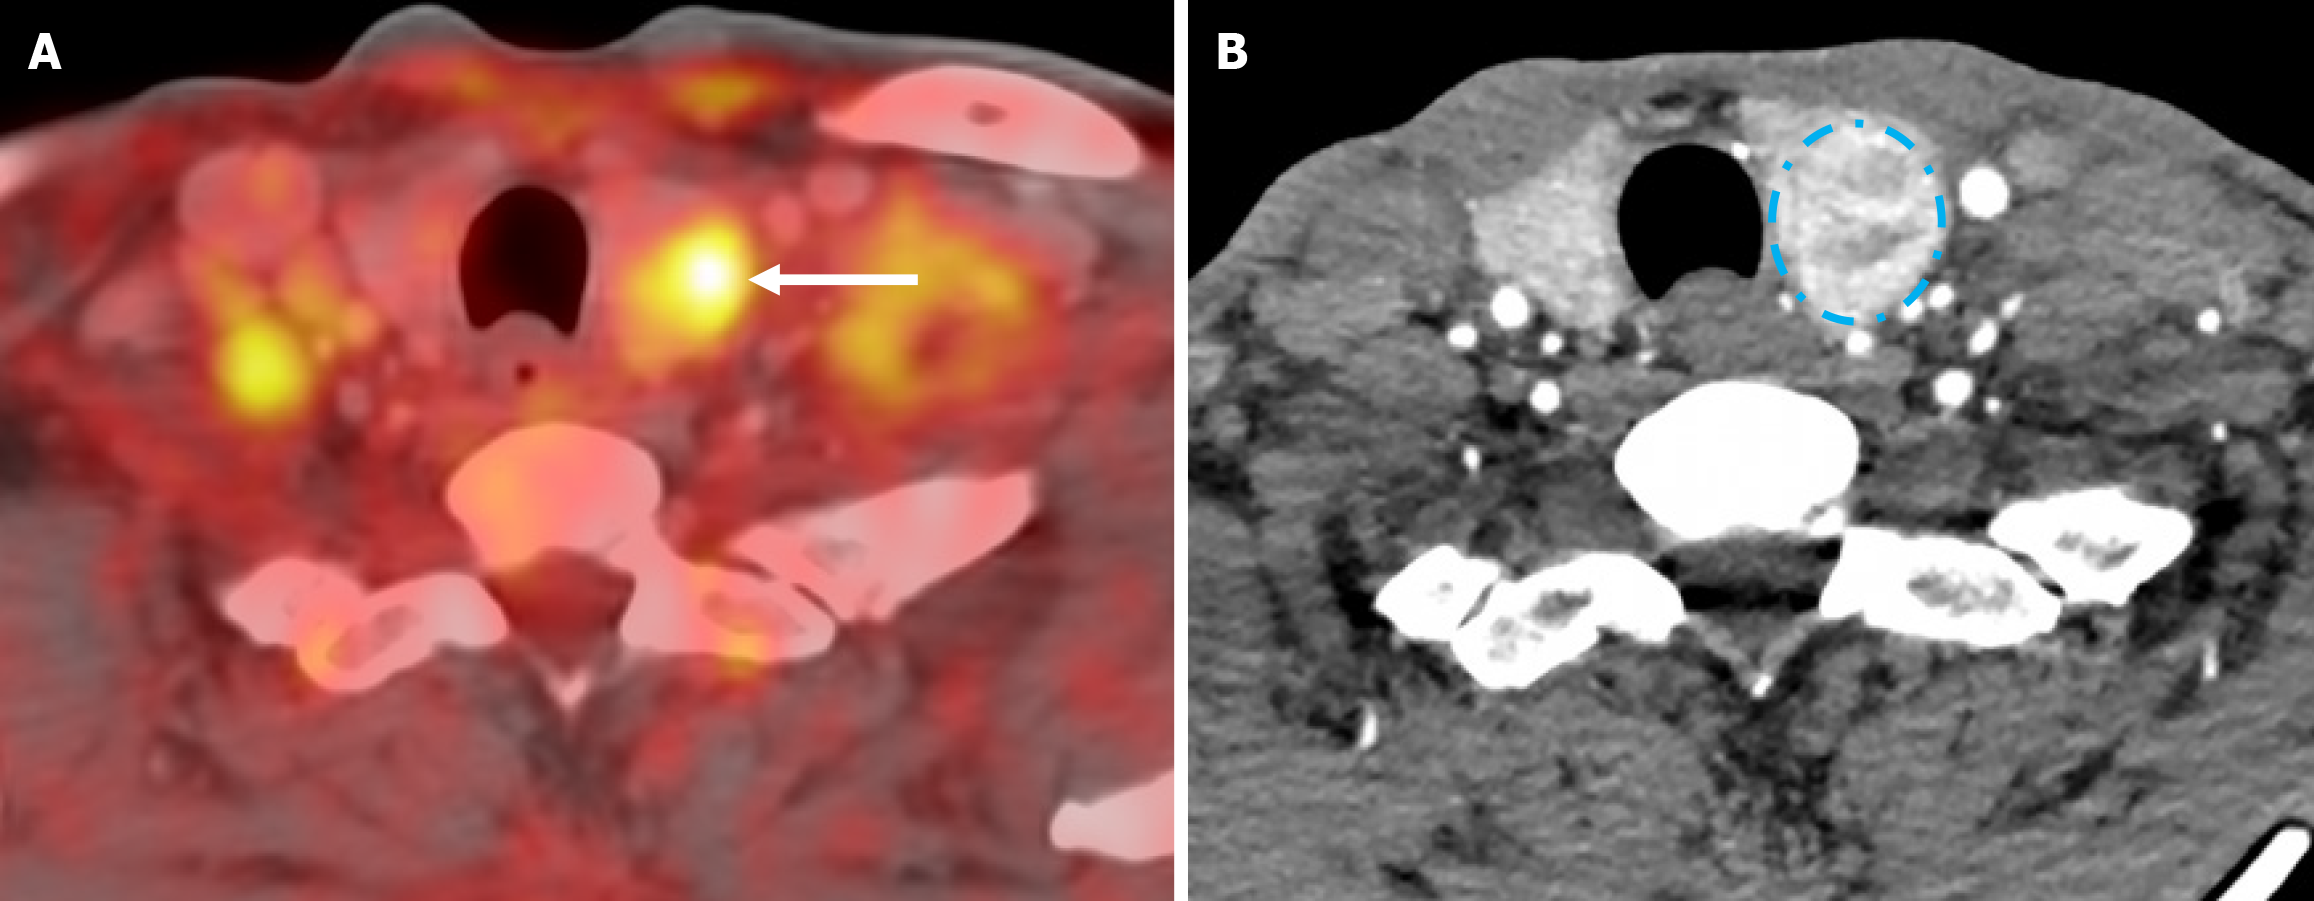

Figure 7 Positron emission tomography/computed tomography (level of the neck).

A: Axial view showing hypermetabolic left thyroid nodule (arrows); B: Contrast enhanced computed tomography neck axial showing heterogeneously enhancing left thyroid nodule.